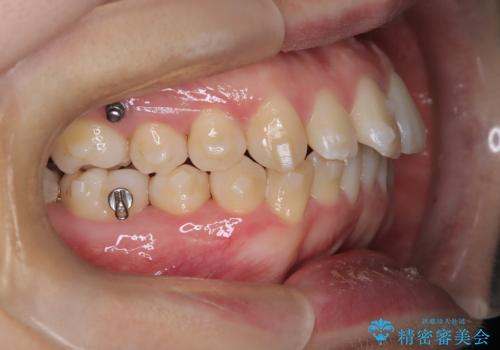

抜歯をせずに口元の突出感を改善するためには、奥歯を後方に動かして前歯を引くスペースをつくる必要があります。そこで、インビザラインによるマウスピース矯正に加え、TAD(矯正用アンカースクリュー)を併用する治療計画を立てました。TADを固定源とすることで、効率的に奥歯を後方へ動かし、非抜歯でも前歯をしっかり引き下げることが可能になります。

治療はまず精密スキャンとシミュレーションを行い、TADを使用して奥歯を遠心移動(後方へスライド)させる設計を組み込みました。マウスピースは計画に沿って順次交換し、TADと連結しながらコントロールすることで、歯列全体を無理なく整えていきました。